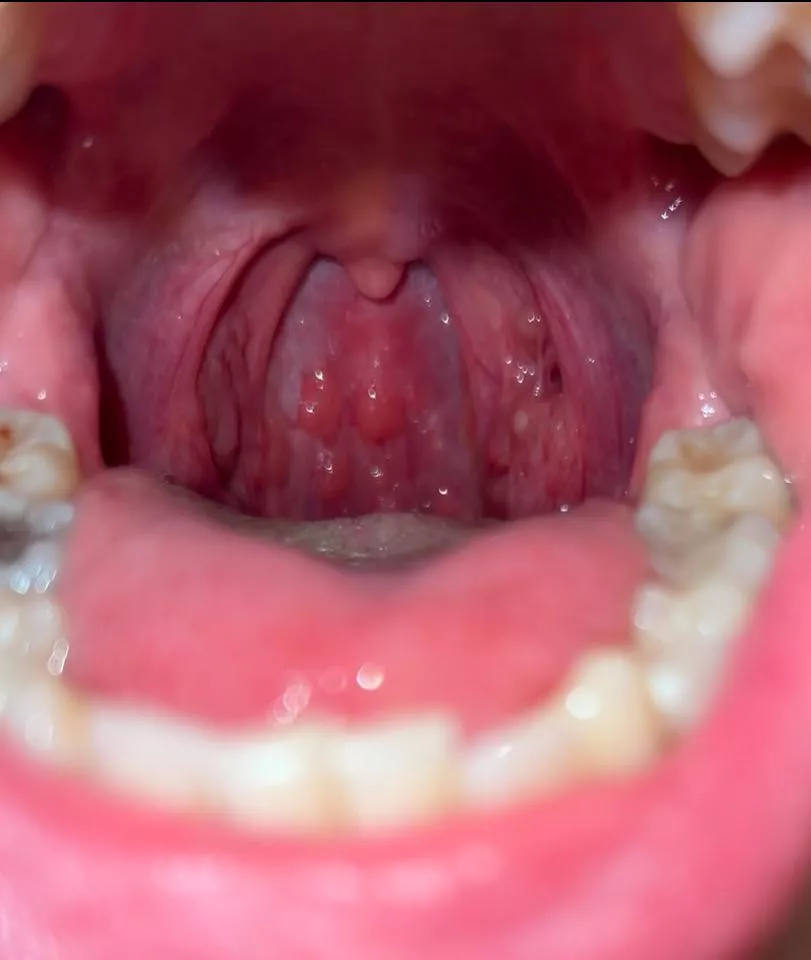

What are these red bumps at the back of my throat? nudes

Category: medical